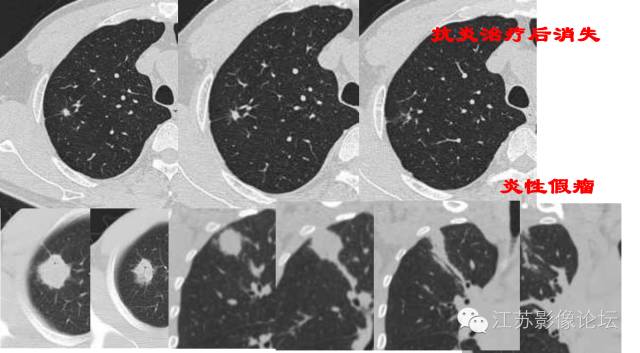

倍增时间是指肿瘤体积增加1倍的时间,常把球形病灶的直径增加25%所需的时间作为倍增时间。实性恶性结节的倍增时间为40-360天,良性结节为小于1个月或大于16个月。